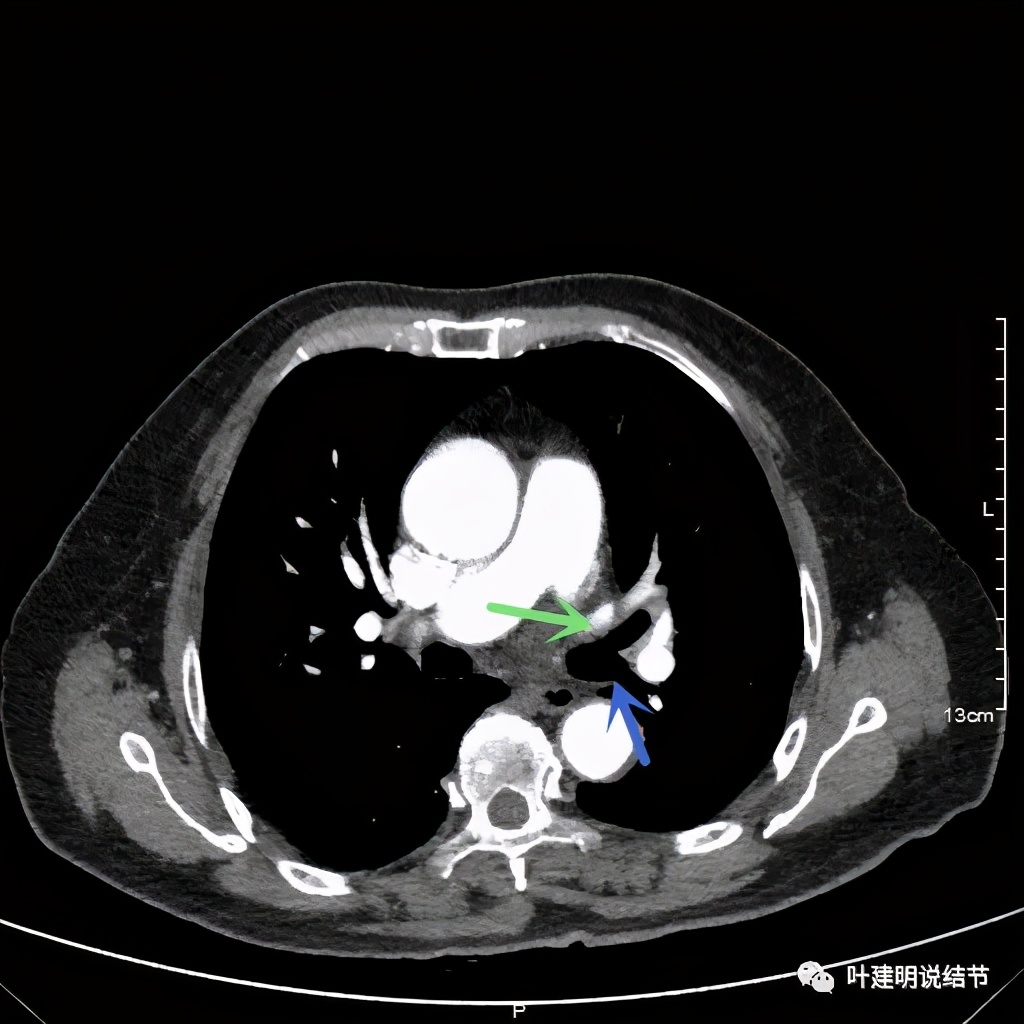

左上肺基本已经不见肿瘤,只在主动脉旁少许软组织影

上图示主动脉弓水平仍见软组织影

上图示肿瘤部位仍与肺动脉关系密切,似乎未能脱开,红色示肿瘤处

上图绿色示左上叶支气管,蓝色示下叶支气管开口处